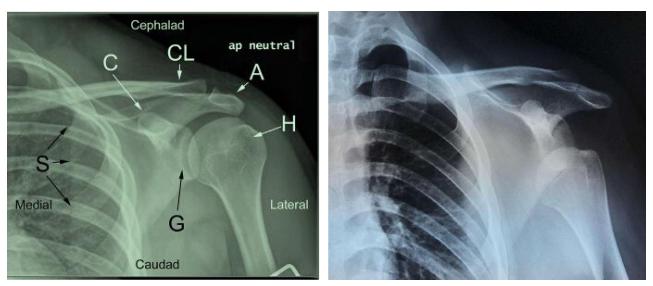

当患者摔伤时:会伴有肩关节韧带,骨性结构的损伤